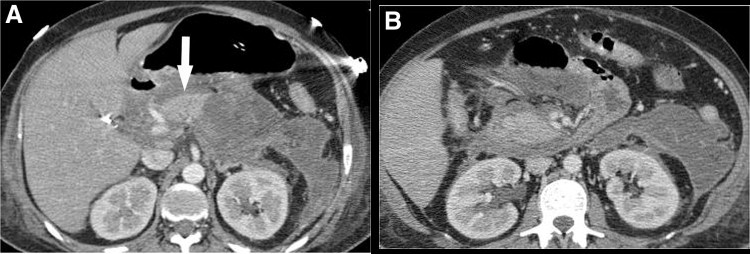

Paciente con pancreatitis aguda. En Tomografía Axial Computerizada (TAC) realizada a las 72 horas de ingreso se aprecia una necrosis del 50% del páncreas. A la 3ª semana de ingreso el paciente comienza con fiebre elevada y leucocitosis. Se solicita radiografía de tórax urgente y sedimento urinario, siendo ambos normales. Señale el siguiente paso a seguir:

La respuesta correcta es la 1 aunque las últimas recomendaciones sobre el manejo de la pancreatitis aguda grave desaconsejan la PAAF por el riesgo de infección del necrosis estéril. El manejo actual se rige por el tratamiento escalonado. En la situación descrita en la pregunta el tratamiento actual es comenzar con antibióticos y valorar respuesta.